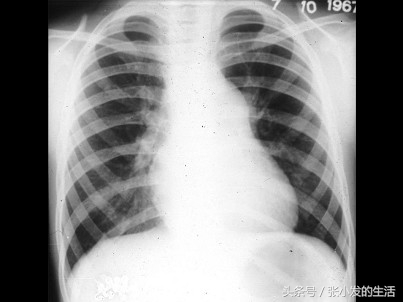

82[单选题]男孩,8岁。体检时发现胸骨左缘第2肋间有粗糙喷射性全收缩期杂音,向颈部传导,肺动脉瓣区第2音减弱。经右心导管检查,证实为中度肺动脉瓣狭窄。进行X线检查,如图所示,下列哪一项不是特点 ( )

A.有时右心房增大

B.右心室有不同程度增大

C.肺动脉段多平直

D.肺动脉总干膨出

E.肺血减少,肺野清晰

正确答案:C